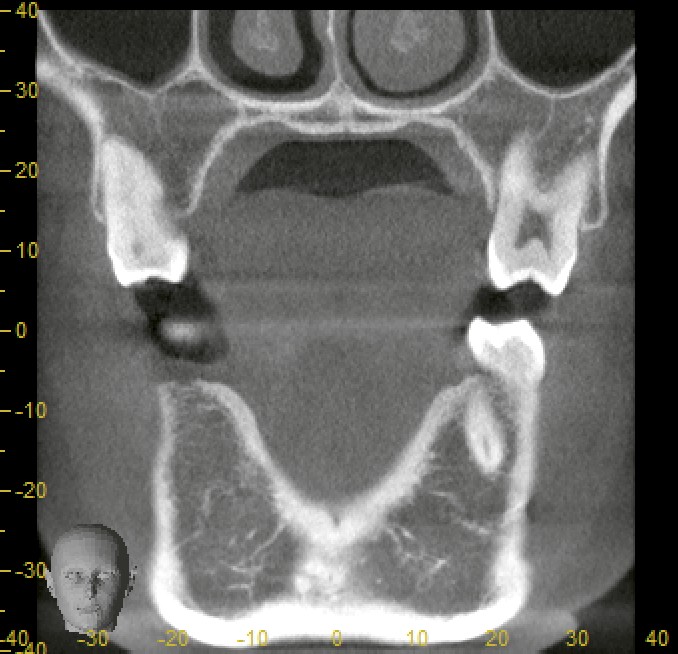

CT・パノラマレントゲンで確認すると、

* 骨幅・骨量ともに十分

* 大きな骨欠損もなし

と良好な条件でした。

* 骨造成が必要な場合

* 神経や隣接歯根に近い場合

* 骨形態が複雑な場合

当院ではCTによる精密診断を行い、「低侵襲インプラント」が可能かどうかをしっかり判断しています。